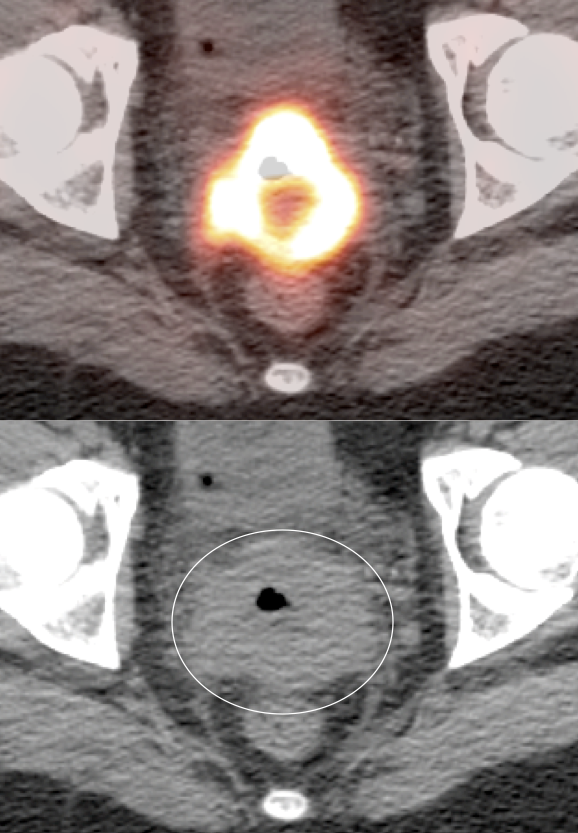

Value of PET/CT Scan for Cervical Cancer

• Valuable diagnostic tool for locally advanced disease, to determine nodal status and potential distant metastatic disease (if no evidence of regional or distant disease, initial management is surgical).

• PET/CT has high sensitivity (>80%) and high specificity (>90%) for metastatic lymph nodes ≥ 8.0 mm.

Indicator of Prognosis: Evidence suggests the more intensely avid the primary tumor, the poorer the patient prognosis.

Directs Radiation Therapy Planning: External beam radiation and brachytherapy planning can be directed from the acquired PET/CT data.

The size, metabolic activity & location of the primary lesion and representative metastatic lesions are reported.

Primary Lesion:

• Nearly every cervical cancer ≥ 8.0 mm is intensely FDG avid (MRI, however, is still considered the best modality for evaluating tumor size and invasion).